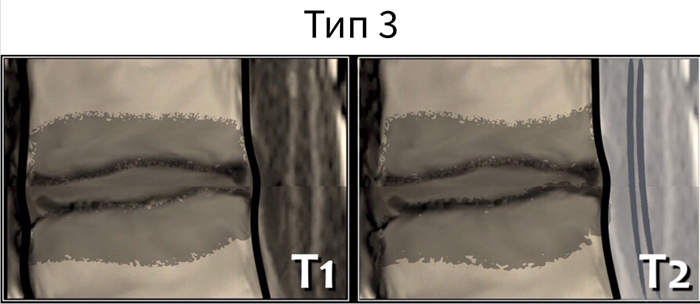

Классификация по типу Modic

Изменения по типу Modic представляют собой классификацию изменений МРТ-сигнала замыкательных пластинок тел позвонков. В 1988 году Майкл Модик описал изменения по типу асептического спондилита. Значимость этих изменений, носящих название Modic, остается предметом дискуссий до сих пор. Представленные изменения замыкательных пластинок и структуры костного мозга тесно связаны с типичным дегенеративным процессом поясничного отдела позвоночника.

В общей характеристике дегенеративных изменений в поясничном отделе позвоночника необходимо обязательно учитывать и изменения в прилежащих к межпозвонковому диску (МПД) частях тел позвонков. Данные изменения могут являться причиной возникновения поясничных болей. При анализе данных магнитно-резонансной томографии (МРТ) используется классификация изменений, предложенная М. Modic.

Классификация изменений костного мозга тел позвонков, в прилежащих к МПД областях по Modic определялась следующим образом на сагиттальных Т1- взвешенных изображениях (Т1ВИ) и Т2- взвешенных изображениях (Т2ВИ):

Тип I - зоны низкой интенсивности МР-сигнала на T1ВИ и высокой интенсивности на T2ВИ по сравнению с костным мозгом, которые соответствуют гиперваскуляризации фиброзной ткани, изменениям вследствие воспаления и отека;

Тип II- высокая интенсивность МР-сигнала на Т1ВИ и Т2ВИ вследствие жировой дегенерации костного мозга;

Тип III - низкая интенсивность МР-сигнала на Т1ВИ и Т2ВИ – появление реактивных склеротических изменений в губчатом веществе тел позвонков.